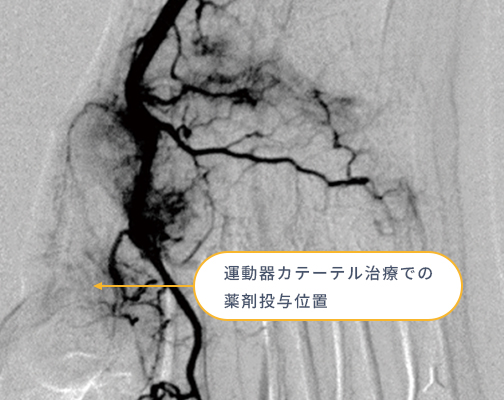

モヤモヤ血管の発生

治りきらない状態が続くと、炎症部位に「モヤモヤ血管」と呼ばれる異常な血管が発生します。これが慢性的な痛みの原因になります。

神経の過敏化

モヤモヤ血管の周囲には痛みを感じる神経が増え、わずかな刺激でも痛みを感じやすい状態になります。